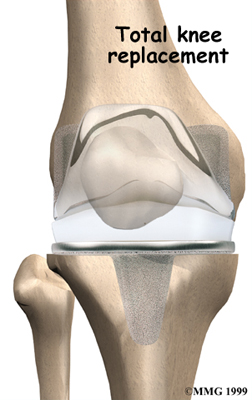

Artificial Knee Replacement

An artificial knee replacement is the ultimate solution for advanced knee OA.

Surgeons prefer not to put a new knee joint in patients younger than 60. This is because younger patients are generally more active and might put too much stress on the joint, causing it to loosen or even crack. A revision surgery to replace a damaged prosthesis is harder to do, has more possible complications, and is usually less successful than a first-time joint replacement surgery.

Related Document: FYZICAL Powell's Guide to Artificial Joint Replacement of the Knee